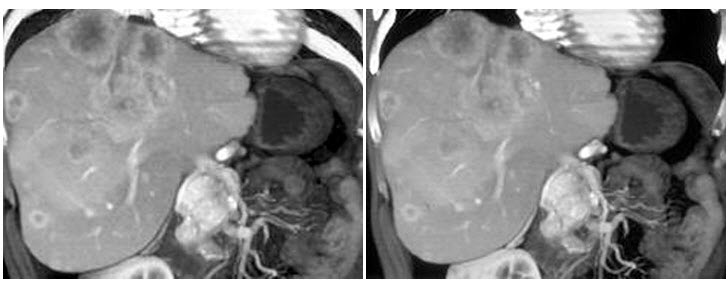

男,48岁,胃癌术后1年,未化疗,CT检查如图所示,最可能的诊断为()

A、肝癌

B、肝转移癌

C、肝血管瘤

D、肝脓肿

E、肝囊肿

B